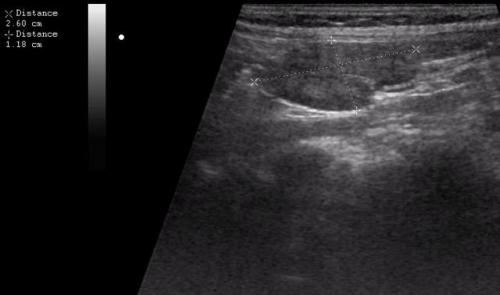

- УЗИ-диагностика и рентгенологическое исследование. Эхопризнаками мезаденита будут увеличение брыжеечных лимфоузлов свыше 5 мм в диаметре.

Эхопризнаком мезаденита является увеличение мезентериальных лимфоузлов - Компьютерная томография используется в более тяжёлых случаях.

Эхопризнаком мезаденита является увеличение мезентериальных лимфоузлов